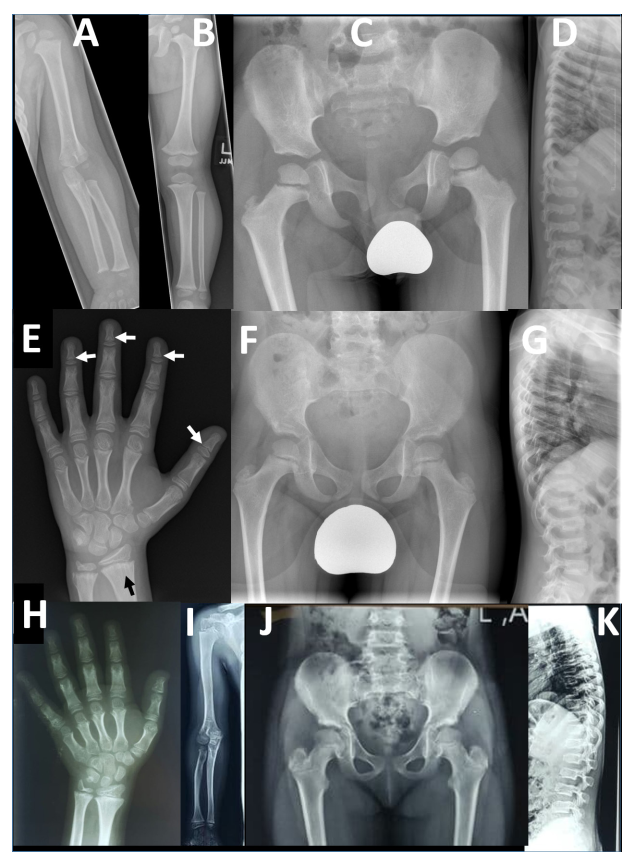

本研究提供了两个家系的详细表型信息,并与两个已发表的病例进行了比较。F2-V-3的放射学发现与之前描述的“先证者1”的放射学发现非常相似,这并不令人惊讶,因为这两个人都有相同的纯合子p.Arg569*。相反,PRKG2家族1有一致的放射学表型,不同于先前报道的AMDP和AMDM。

两个PRKG2变异家族的影像学表现

本文报告的三兄弟 (F1-IV-3、IV-6和IV-7)除了个别F1-IV-7有轻微的脚趾缩短外,没有肢端缩短 (Acromesomelic shortening)的证据。主要发现是颈椎病伴有椎体前突、股骨颈细长、干骺端不规则 (最明显的是桡骨和尺骨)和横纹(Striations)。其中一个儿童的远端指骨干骺端呈圆锥形,但是不显著。综上所述,家族1表现为以脊柱干骺端发育不良 (Spondylometaphyseal dysplasia)为特征的骨骼表型,而不是像AMDP和AMDM所预期的肢端发育不全。

F1- IV- 7的额外影像学表现